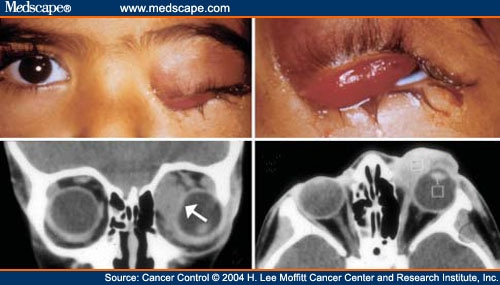

Orbital Rhabdomyosarcoma

www.medscape.com

www.medscape.com

rhabdomyosarcoma orbital

Orbital Rhabdomyosarcoma - Page 2

www.medscape.com

www.medscape.com

rhabdomyosarcoma orbital figure